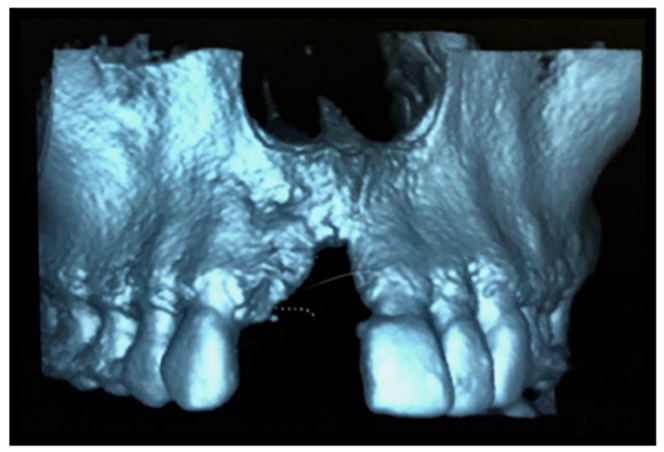

Foi solicitada a tomografia computadorizada total de maxila, com medidas de altura e espessura para planejamento cirúrgico.

Observou-se extenso defeito ósseo nos sentidos horizontais e verticais em pré-maxila (Figuras 2 e 3), sendo necessária a realização de uma extensa regeneração óssea guiada, com enxerto ósseo particulado (Geistlich – Bio-Oss), membrana de PTFE-d com reforço de titânio e membranas de fibrina autógena (LPRF).